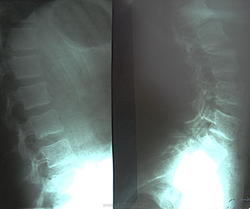

Пол пациента: Женский пол Тип патологии: Травма Область исследования: Скелетно-мышечная система Методы исследования: Rg после тренировки почувствовала жалобы на резкие боли в области крестца. Прошу прощения коллег за качество снимков. У меня возникло подозрение о листезе? https://radiomed.ru/sites/default/files/styles/case_slider_image/public/user/712/sl273623.jpg?itok=1nQbEQ2A ID:13720 Wed, 27/04/2011 - 19:55 #1 Nela Offline Last seen: 6 years 2 months ago Joined: 12.05.2009 - 20:43 Posts: 1847 Листез есть, на мой взгляд. А нельзя без вспышки сфотографировать? Wed, 27/04/2011 - 20:47 #2 Шаба Offline Last seen: 3 years 5 months ago Joined: 19.08.2010 - 22:01 Posts: 122 за листез Wed, 27/04/2011 - 20:49 #3 Глазков Игорь А... Offline Last seen: 10 months 2 weeks ago Joined: 19.12.2008 - 20:41 Posts: 1597 вспышки, но что-то не выходит лучше. Прийди к Себе Wed, 27/04/2011 - 21:07 #4 Ola-la Offline Last seen: 11 months 1 week ago Joined: 06.12.2008 - 09:33 Posts: 1786 Похоже да, истинный спондилолистез. https://www.instagram.com/pediatricradiology/ Wed, 27/04/2011 - 22:55 #5 Rg-Doc Offline Last seen: 8 years 10 months ago Joined: 22.03.2008 - 12:25 Posts: 333 Ola-la wrote: Похоже да, истинный спондилолистез. А где похоже, что истинный? Thu, 28/04/2011 - 07:33 #6 Rex Offline Last seen: 14 years 8 months ago Joined: 26.04.2011 - 21:03 Posts: 35 ЗдесьПриложения: Даже когда уверен на 100%, непременно подвернется исключение из правил... Thu, 28/04/2011 - 08:48 #7 Rg-Doc Offline Last seen: 8 years 10 months ago Joined: 22.03.2008 - 12:25 Posts: 333 Игорь Артурович, не могли бы Вы еще раз сфотографировать снимки с более лучшим качеством? Thu, 28/04/2011 - 18:40 #8 Глазков Игорь А... Offline Last seen: 10 months 2 weeks ago Joined: 19.12.2008 - 20:41 Posts: 1597 придёт. что должно случиться. то обязательно переснему. Прийди к Себе Thu, 28/04/2011 - 21:20 #9 Игорь Иванович Offline Last seen: 3 years 10 months ago Joined: 23.01.2010 - 14:56 Posts: 3695 Только этот спондилолистез не нужно связывать с тренировкой.

Листез есть, на мой взгляд. А нельзя без вспышки сфотографировать?

Похоже да, истинный спондилолистез.

Только этот спондилолистез не нужно связывать с тренировкой.